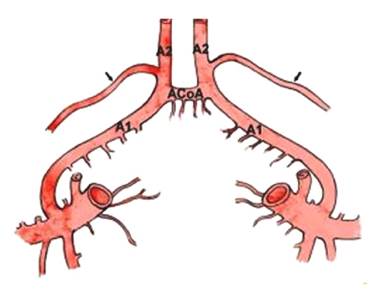

Recurrent Artery of

Heubner – can have variable origin

before or after A1/A2 junction